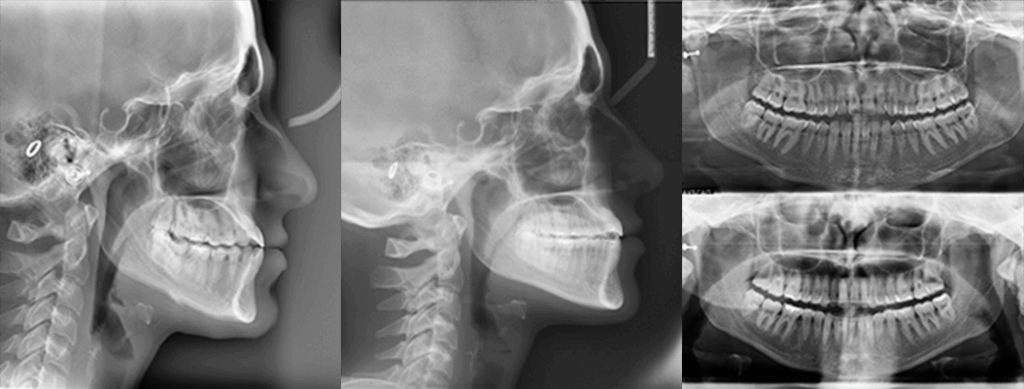

A 22-year-old female patient presented with a Class III malocclusion. She does not like her own profile. Her facial profile was straight with a slightly retrusive maxilla, the upper incisors were within normal inclination, and the lower incisors were retroclined. Bolton discrepency is on mandible for 6 teeth. A retruded upper lip and a normally positioned lower lip were noted. There was also a marked lack of midface support, and the constricted dental arches resulted in a narrow smile and pronounced dark buccal corridors.

Gaining overjet: Use forward-activating archwires to advance the proclined upper incisors and establish an adequate overjet.

Compensating proclination: Place retrocline brackets on UL2, UL1, UR1, and UR2 to counterbalance the created proclination.

Managing Bolton excess: Address the mandibular Bolton excess by increasing the mesiodistal expression on the upper canines, selecting procline brackets for UL3 and UR3.

Lower anterior control: To compensate for potential retroclination of the lower incisors during consolidation, use procline brackets on L3, L2, and L1 bilaterally.

At the end of treatment, the patient’s occlusion was corrected to Class I molar and canine relationships with a physiological overjet and overbite. Irregularities in both arches were eliminated, arch forms were coordinated, and incisor torque was effectively controlled to position the roots centrally within the alveolar bone, enhancing stability. Satisfactory intercuspation was achieved in both the anterior and posterior segments, with maintenance of midline coincidence and periodontal health throughout treatment. The case was finished and transitioned into the retention phase using fixed retainers in the maxillary and mandibular anterior regions.